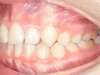

Avant

Après